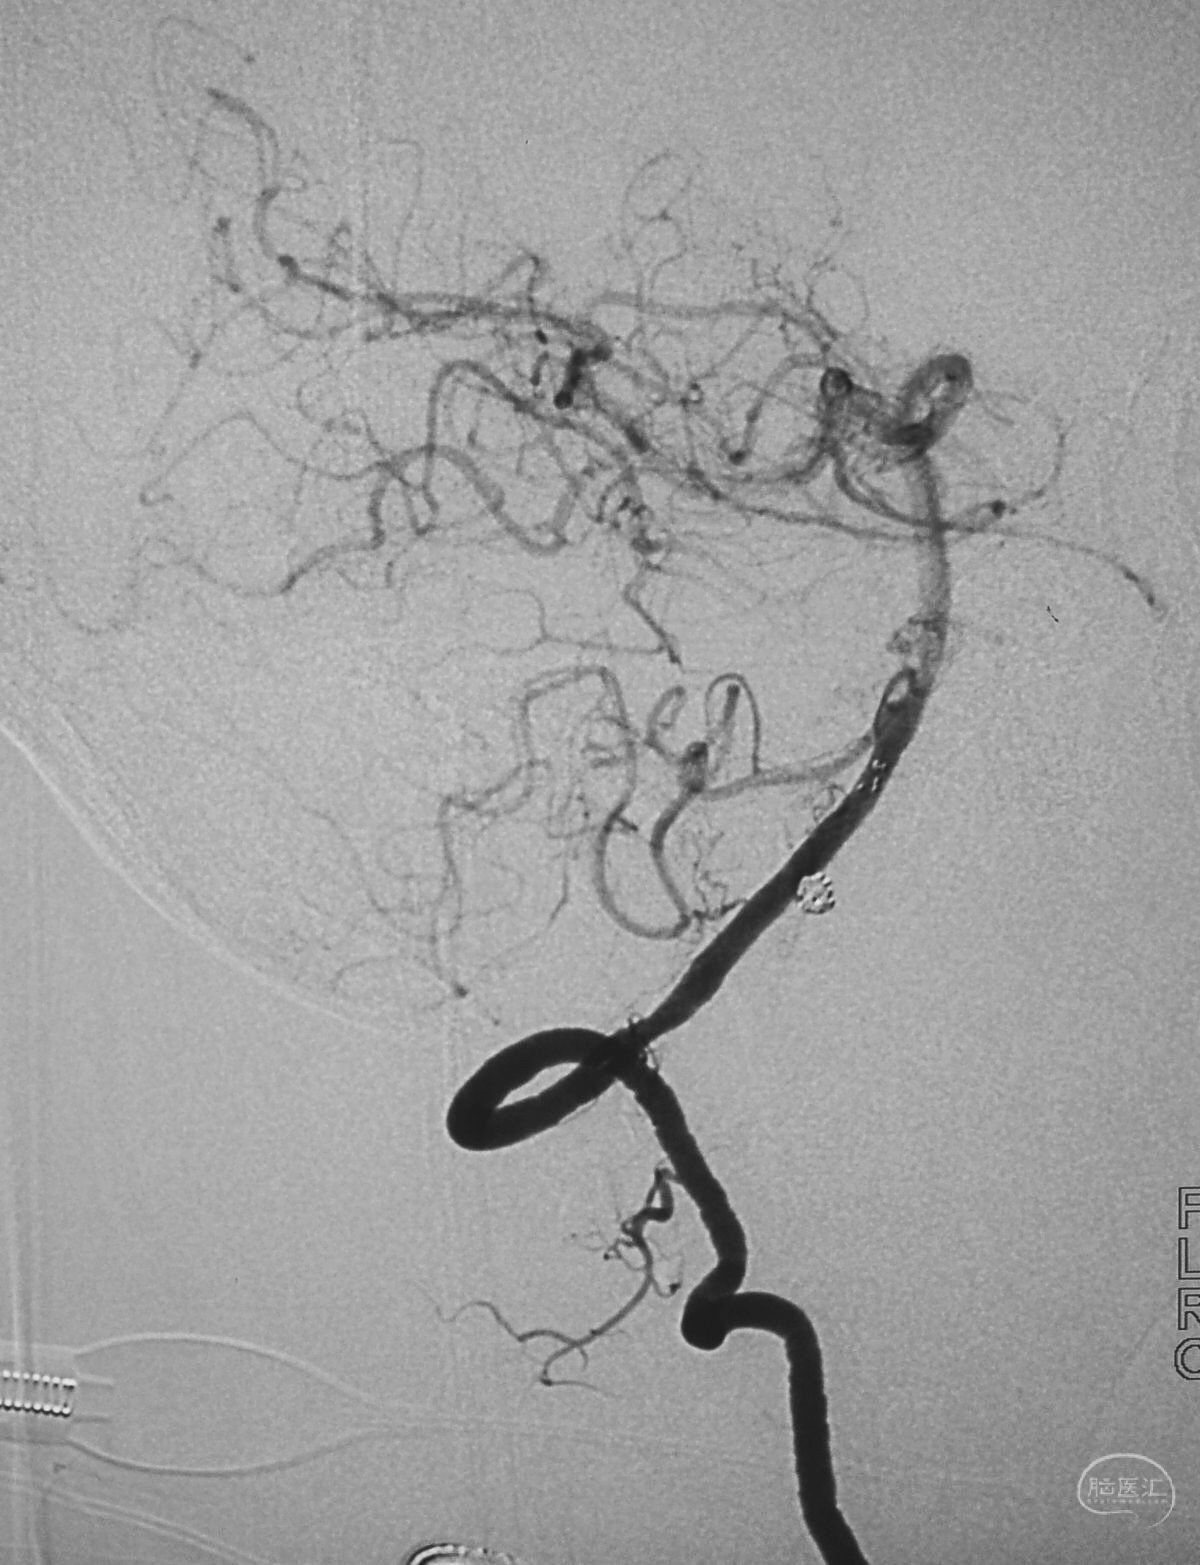

术后右椎动脉工作位造影,

以及正位造影显示动脉瘤完全栓塞,载瘤动脉畅通。

解脱第一枚Solitaire 4×20支架后,套叠置入第二枚Solitaire 4×20支架,置入两枚支架的原因是考虑该瘤是夹层动脉瘤,多支架能够强化血流导向作用,有利于夹层愈合。